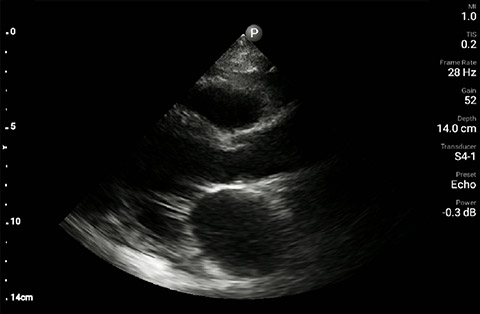

The patient had reduced LV systolic function without new or severe valvular pathology, a dilated, non-collapsing IVC, and diffuse B lines (left greater than right) on lung ultrasound imaging.

Apical 4-chamber

Parasternal long-axis